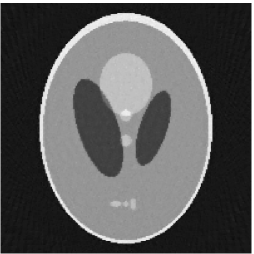

Noiseless projection data: Since the ghost in this phantom is invisible at 22 directions [10, 11], the reconstruction images usually suffer from artifacts. in our simulations, the projection data were collected in 112 and 82 directions: 90 and 60 with equal angle increments from to and 22 specified views in which the ghost is invisible [10]. Iteration procedures were terminated when for the noiseless projections.

The reconstruction images from the noiseless projection data were shown in the Fig. 6. For comparison, Table 3 present the iterations, MSE, Res and running time(RT) of different reconstruction results.

| Algorithm | TV-S | TV-PPS | TV-S | TV-PPS |

|---|---|---|---|---|

| projections | 112 | 112 | 82 | 82 |

| iterations | 24 | 19 | 33 | 32 |

| MSEs | 0.0056 | 0.0026 | 0.0108 | 0.0083 |

| RT(min) | 16.82 | 13.89 | 10.83 | 10.87 |